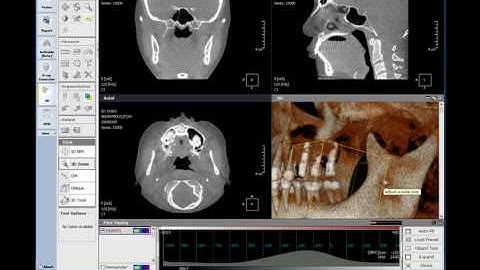

OnDemand3D Tool Tip - CPR(3D module)